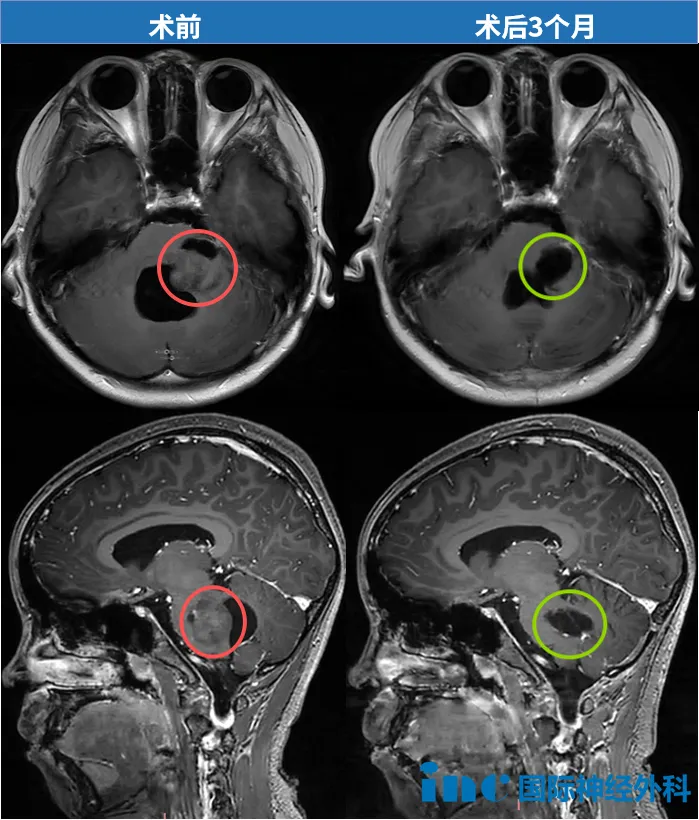

巴特朗菲教授详细评估影像资料后,明确表示可实现肿瘤全切。家属决定在苏州大学附属儿童医院进行二次手术,由巴特朗菲教授主刀,王杭州主任团队配合完成。术后患儿意识清醒返回普通病房,未进入ICU监护。术后第二天(4月4日)即能下床活动,虽步态不稳但可自理如厕。

康复过程与随访结果

术后10天观察显示,患儿神经功能持续改善,行走稳定性日益提高。术后3个月随访影像证实肿瘤完全切除,磁共振检查未发现相关并发症。巴特朗菲教授在随访邮件中特别指出,虽然肿瘤质地较硬增加了手术难度,但最终实现了满意的切除效果。